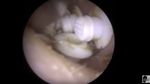

Kotoran telinga ini berwarna putih namun sedikit mengeras. (Foto: YouTube)